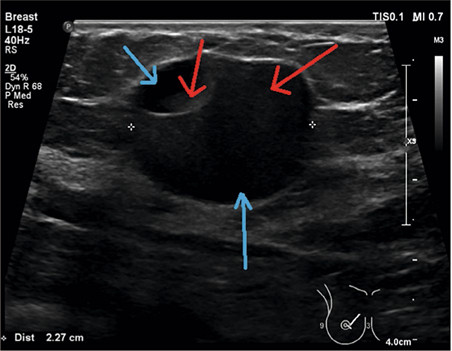

Mastitis? Denk aan galactocele

Jaarlijks komt er per huisartsenpraktijk 1 tot 2 keer een patiënte met mastitis op het spreekuur, waarbij het meestal om kraamvrouwen gaat. De ontsteking wordt veroorzaakt door een infectie of door stase van melk in de melkgangen. In dat laatste geval ontstaat er door de ontstekingsreactie een acute cellulitis van het interlobulaire borstklierweefsel. Er is vaak sprake van unilaterale borstpijn, roodheid en zwelling met algehele malaise en koorts. Het is lastig om klinisch onderscheid te maken tussen een infectieuze en een andere oorzaak van de borstontsteking. Mogelijk stellen huisartsen de diagnose infectieuze mastitis bij kraamvrouwen daardoor te vaak.